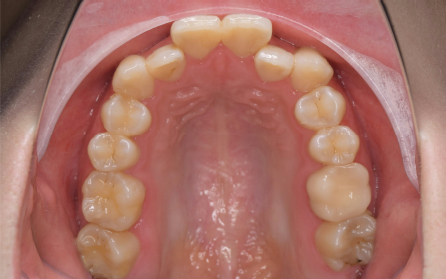

8歳 女児

主訴 「前歯がでこぼこで、反対になっている」

診断 「側切歯のクロスバイトを伴う叢生症例」

第一期治療(成長期の治療)では、狭窄歯列による上下前歯部の叢生の改善のため、歯列弓の拡大を行いました。患者さんの協力(マウスピースの使用状況等)も良好で、歯列の拡大により得られたスペースは十分で側切歯(2番目の歯)のクロスバイトも改善されました。治療期間は15か月で、今後は乳歯から永久歯への生え変わりの経過観察に移行します。すべての歯が永久歯になる頃(12歳頃)に第二期治療(仕上げの治療)が必要になることもありますが、この患者さんの場合はその可能性は低いと考えられます。